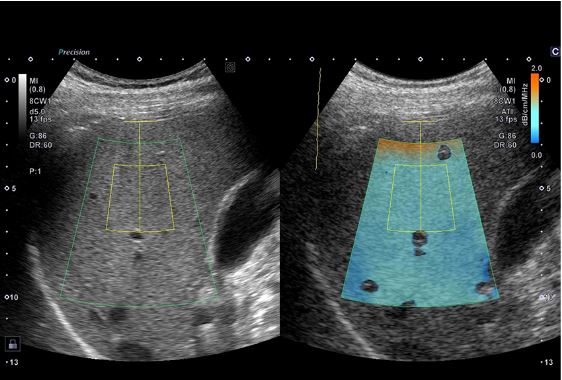

Технологія Attenuation Imaging (ATI) – кількісна оцінка стеатозу печінки, візуально показує ослаблення ультразвуку в печінці.

Еластографія зсувної хвилі (SWE) візуалізує швидкість зсувної хвилі та еластичність тканини для аналізу фіброзу печінки.

Конвексний датчик PVU-475BTW (8CW1)

Монокристалічний конвексний датчик забезпечує зображення високої роздільної здатності для абдомінальних досліджень. Висока щільність елементів у поєднанні з iBeam+ забезпечує ультрашироке поле огляду 140°, яке наразі доступне лише для Aplio i-серії.